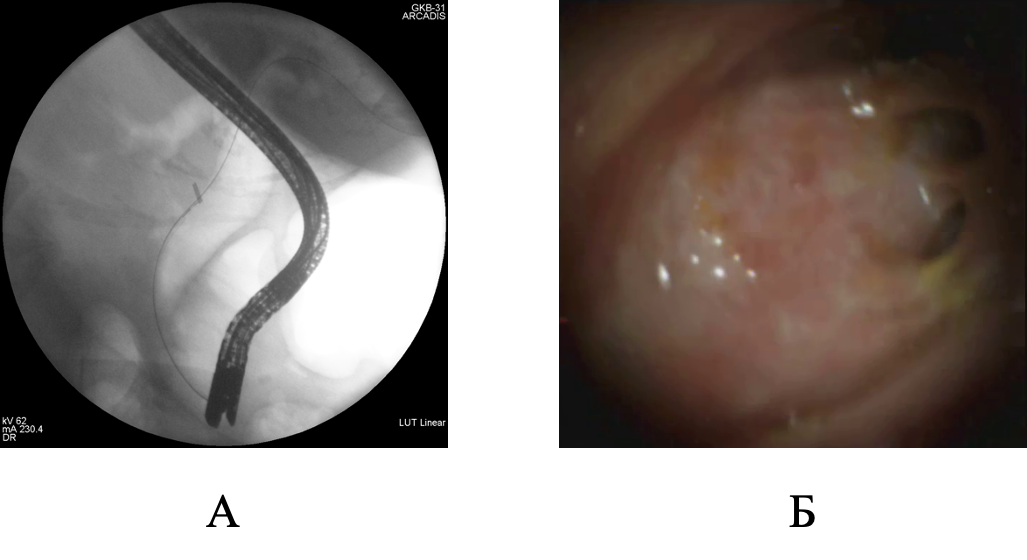

Представлено клиническое наблюдение успешного этапного эндоскопического лечения при гигантском множественном холедохолитиазе. Традиционное хирургическое вмешательство было противопоказано пациентке ввиду выраженных сопутствующих заболеваний и большого анестезиологического риска. Базовым методом мини-инвазивного лечения была контактная литотрипсия, дополненная баллонной дилатацией зоны эндоскопической папиллосфинктеротомии и механической внутрипротоковой литотрипсией. Применение контактной литотрипсии при пероральной транспапиллярной холангиоскопии в сочетании с другими современными способами эндоскопического лечения холедохолитиаза обладает хорошим техническим и клиническим эффектом даже при гигантских размерах билиарных конкрементов.

Будзинский С.А., Шаповальянц С.Г., Воробьева Е.А., Козлова П.С., Соловьев Н.С., Платонова Е.Н., Федоров Е.Д. Успешное эндоскопическое лечение гигантского множественного холедохолитиаза с применением пероральной транспапиллярной холангиоскопии и внутрипротоковой контактной литотрипсии. Анналы хирургической гепатологии. 2023;28(1):109-115. https://doi.org/10.16931/1995-5464.2023-1-109-115

Budzinskiy S.A., Shapovalyants S.G., Vorobyova E.A., Kozlova P.S., Solovjev N.S., Platonova E.N., Fedorov E.D. Successful endoscopic treatment of giant multiple choledocholithiasis using oral transpapillary cholangioscopy and intraductal contact lithotripsy. Annaly khirurgicheskoy gepatologii = Annals of HPB Surgery. 2023;28(1):109-115. (In Russ.) https://doi.org/10.16931/1995-5464.2023-1-109-115